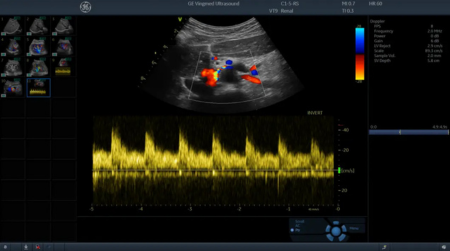

Vivid T8 GE HealthСare объединяет признанное качество визуализации в кардиологии, характерное для линейки систем Vivid, и выдающиеся возможности широкого использования в общей диагностике.

• Поддержка режимов исследования: 2D, ЦДК, спектральный допплер, тканевой спектральный и цветовой допплер